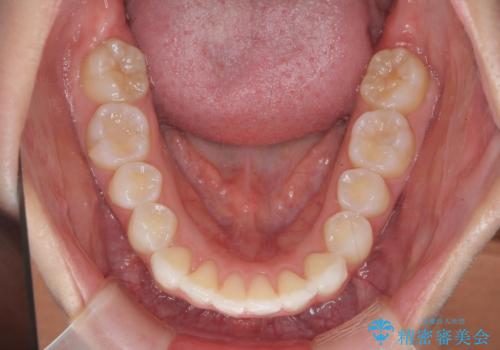

前歯のがたつき気になる。インビザラインモデレート

- 前歯のがたつきが気になるとの事で来院。

噛み合わせを確認したところ上の歯が全体的に前にある状態でした。

患者様は2のプランを選ばれたのでインビザラインモデレートで治療を行いました。

ガタつきがなくなり満足して頂けました。

矯正後は補綴装置をつけないと後戻りしてしまう可能性があるので

補綴装置をしっかりと装着する必要があります。